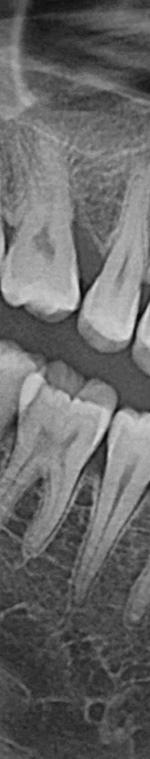

턱 뼈와 치아 사이에 공간이 충분하지 않기 때문에 누워서 올라오거나 매복되어 자라는 경우가 많았어요. 반포치과를 찾는 분들의 사랑니의 경우 매복된 경우도 많고 이가 완전히 잇몸 밖으로 나오지 않아서 일반 치과에서는 발치가 어려웠어요. 사랑니발치가 왜 필요한지 가끔 의문을 가지는 분이 계셨어요. 사랑니발치를 왜 해야 하는지 알려드리겠어요. 사랑니는 다른 치아처럼 바르게 나는 경우도 드물게 있긴 하지만 대부분 어금니 쪽으로 기울어져서 올라오거나, 완전히 수평으로 누워서 자라는 경우도 있었어요. 누워서 자라는 치아는 옆의 치아를 밀어 치열이 비뚤어지고 부정교합을 유발했어요.

사랑니가 90도로 누워서 난 경우는 수평 매복, 뼈나 잇몸에 사랑니가 완전히 덮여서 아예 보이지 않는 경우는 완전 매복, 일부분만 잇몸이나 뼈에 덮여있는 경우 부분매복이라고 했어요. 대부분의 환자분이 이런 매복 중에 한 가지에 해당하기 때문에 시술이 매우 어려웠어요. 특히 사랑니 주변으로는 구강과 관련된 중요한 신경 조직이 인접하여 있기 때문에 고난이도 시술이라고 할 수 있었어요.

사랑니발치를 하기 위해서는 먼저 파노라마 x선 사진을 통해 발치 시 신경에 영향을 줄 수 있는지 확인하는 과정을 진행했어요. 이 과정을 통해서 충분히 의사와 상담을 한 후 처방전을 발급했어요. 이 때 처방전에는 항생제를 포함하여 발치 후 통증을 대비한 진통제를 처방했어요. 환자에게 충분히 설명한 후에 국소마취를 진행하고 마취가 된 다음에 절개를 최대한 덜 하는 방향으로 수술하여 사랑니를 발치했어요.